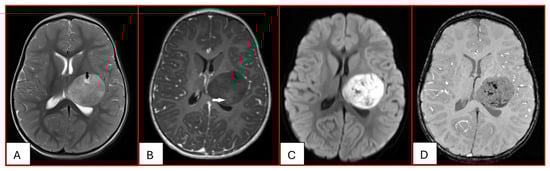

On computed tomography (CT), AT/RTs typically appear hyperdense owing to their high cellularity, and calcifications are frequently identified. Magnetic resonance imaging (MRI) findings are variable on both T1- and T2-weighted sequences; however, restricted diffusion is usually present. Cystic or necrotic components, as well as intratumoral hemorrhage, are common features [15]. Arslanoglu et al. described the presence of eccentrically positioned cysts with peripheral wall enhancement as a potentially distinguishing characteristic of infratentorial AT/RTs (Figure 1). The pattern and degree of contrast enhancement are variable, further reflecting the histopathologic heterogeneity of these neoplasms (Figure 2 and Figure 3). A characteristic pattern of band-like enhancement surrounding a central cystic or necrotic area was observed in 38% of MRIs from a series of 32 patients [16].

Figure 2. Twenty-three-month-old female with ATRT. (A) Axial T2-weighted image reveals a circumscribed supratentorial mass centered in the left deep gray nuclei of heterogeneous intermediate signal with small central cystic/necrotic changes (black arrow). There is no surrounding edema. (B) This mass is predominantly non-enhancing with minimal internal foci of enhancement (white arrow). (C) There is corresponding prominent restricted diffusion. (D) Multiple internal foci of susceptibility are present, which may reflect internal hemorrhage or calcifications.